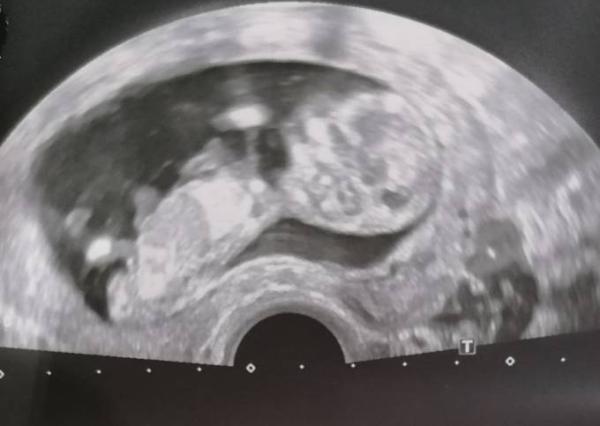

Wir hatten heute Ultraschall. Unser kleines hat sich soooo viel bewegt, umgedreht und rumgeturnt. Man konnte schon alles erkennen, Köpfchen, Hände und Füße, sogar Finger. Hätte nie gedacht, dass das einen so sprachlos machen kann, wirklich schön! :-)

Bild zu Ultraschall 13. SSW - Forum für Juni - Mamis

Ach wie toll wunderschönes Foto hast du bekommen.